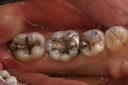

Frank Fukuda #30 pre-op

Frank Fukuda #30 caries removal

Frank Fukuda #30 buccal prep

Frank Fukuda #30 prep

Frank Fukuda #30 finish

Frank Fukuda #30 buccal

Frank Fukuda #30 combined view